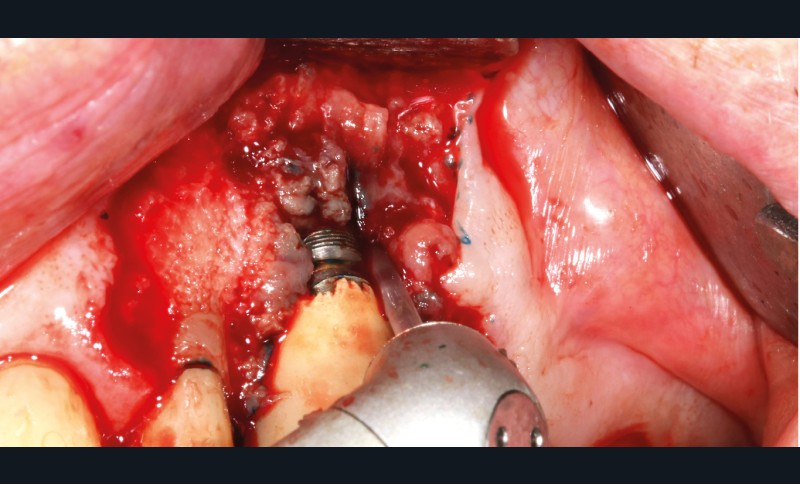

– Le laser Er-YAG, utilisé pour le nettoyage, est un laser avec un milieu actif composé d’yttrium, d’aluminium et de grenat dopé à l’erbium. Avec une longueur d’onde de 2 940 nm situé dans l’infrarouge, le laser Er-YAG est un laser à haute énergie, dont la lumière est absorbée dans l’eau et dans l’hydroxyapatite et qui ne pénètre pas profondément. Ceci permet de couper des tissus mous et des tissus durs, mais également de désorganiser le biofilm bactérie.

C’est un laser idéal pour le traitement chirurgical des péri-implantites. Il permet l’élimination du tissu de granulation à la surface de l’implant et de l’os ainsi qu’une décontamination mécanique par effet photoablatif.– Le laser Diode, utilisé pour la décontamination…